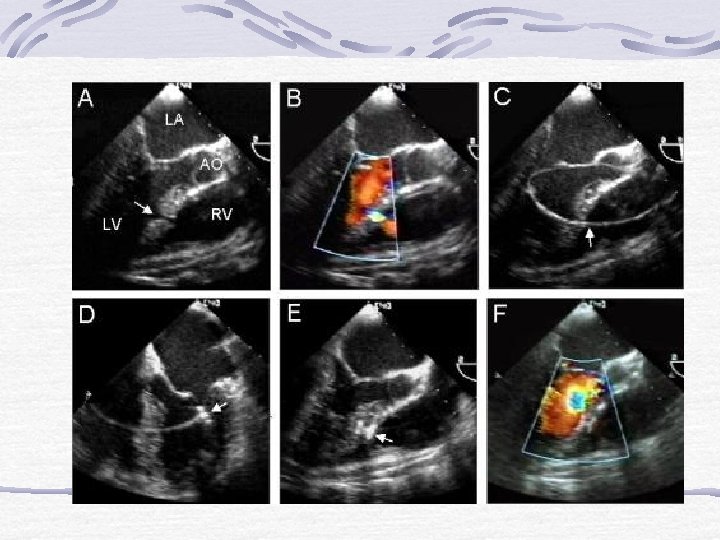

ASD Kapatılması §Sekundum ASD’lerde uygulanabilir. Defekt kenarlarının yeterli büyüklükte olması gereklidir. Ciddi PH varsa kontrendikedir. § §

Helex § Profili küçüktür § Geri alınması kolaydır § Yuvarlak yapısı § § nedeniyle dokulara bası azdır Büyük ASD’lerde kullanılması önerilmemektedir İmplant sayısı henüz azdır

İdeal “Device” §Küçük kılıf §Bırakılma öncesi kontrol §“Self-centering” mekanizma §Ucuz ve kolay uygulama §Bırakıldıktan sonra kolay geri alma §“Low-profile” §Endotelizasyonun sağlanması